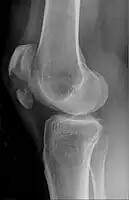

| A fracture of the patella seen on a lateral view | |

Transverse fracture of patella

Comminuted fracture of patella

Osteochondral fracture of patella

Vertical patella fracture